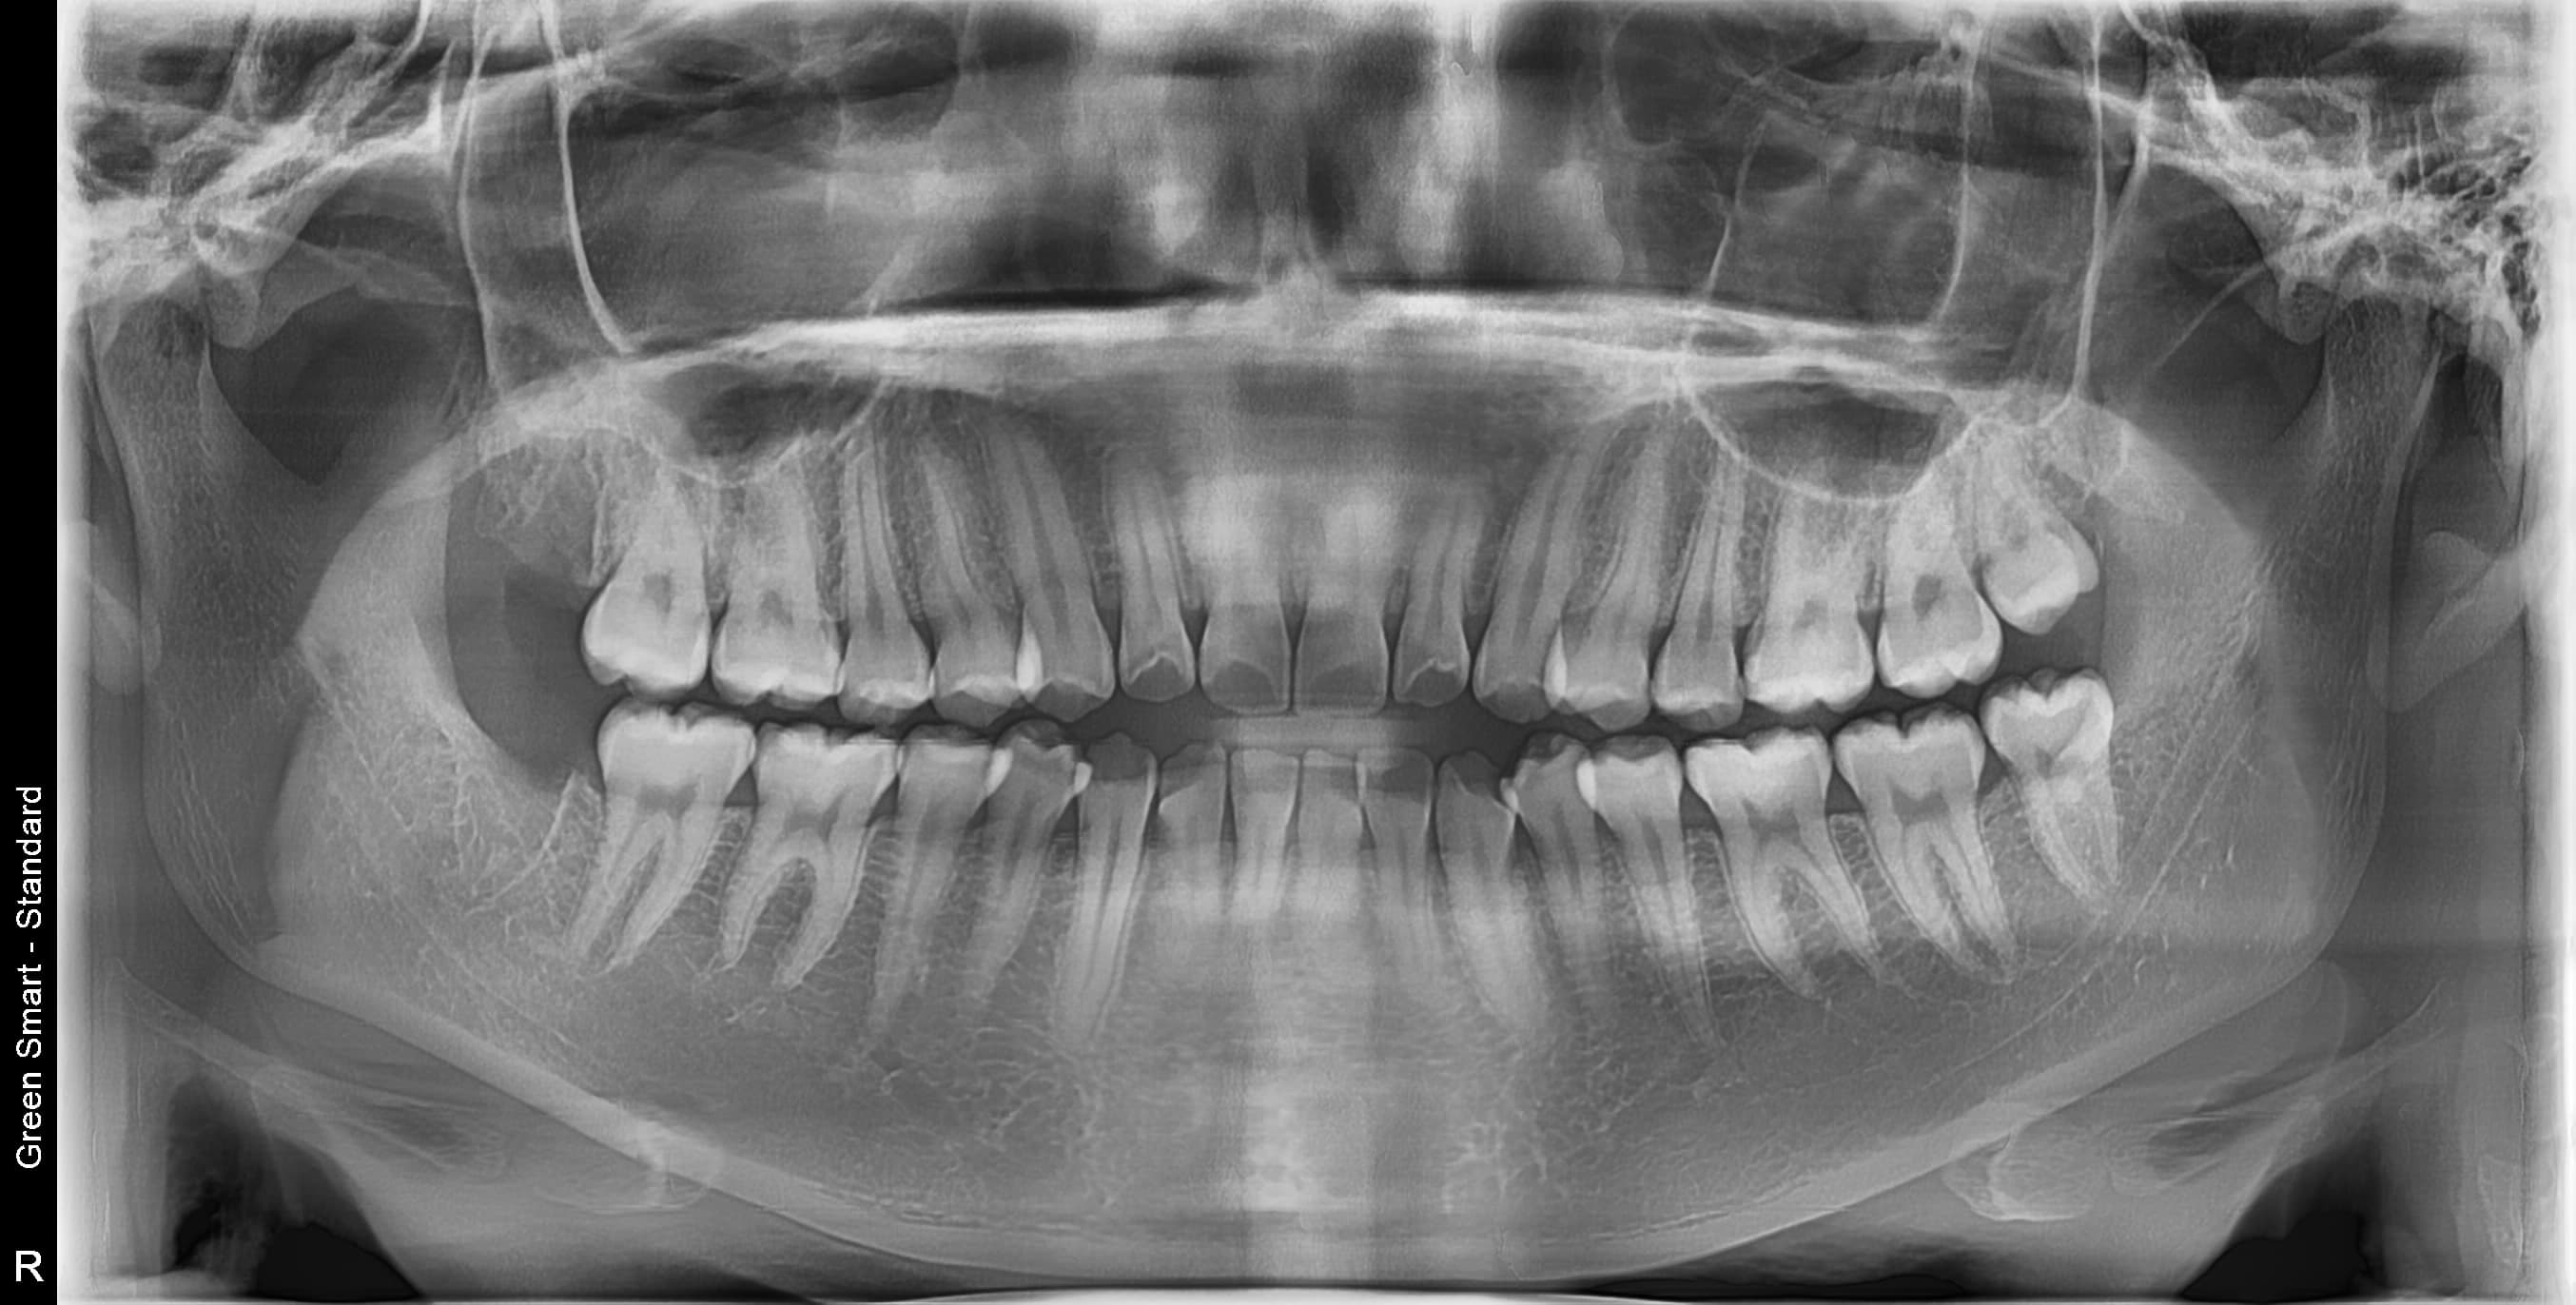

최신 디지털 장비 완비

3D CT, 디지털 스캐너, 디지털 가이드 수술 시스템 등

최첨단 장비로 정밀한 진료를 제공합니다

사랑니 발치, 꼭 해야 하나요?

통증이 없어도 잇몸 속에서 염증, 충치, 치열 불균형을 일으킬 수 있습니다. 3D CT로 정밀 진단 후 필요 여부를 판단하며, 미리 뽑지 않으면 급성 염증, 인접 치아 손상, 턱관절 장애 등의 문제가 발생할 수 있습니다. 젊을수록 회복이 빠르고 합병증 위험이 적습니다.

난이도 높은 사랑니도 뽑을 수 있나요?

네, 가능합니다. 고덕퍼스트치과는 풍부한 발치 경험과 대학병원급 난이도 발치가 가능한 시스템을 갖추고 있습니다. 수평매복, 완전매복 등 일반 치과에서 큰 병원을 권유하는 어려운 케이스도 3D CT 정밀 진단으로 안전하게 발치합니다.